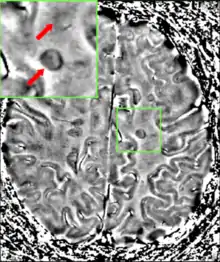

Самі по собі клінічні дані можуть бути достатніми для діагностики множинного склерозу, лише якщо в пацієнта були окремі епізоди, неврологічні симптоми, характерні для цієї хвороби.[45] У тих, хто звернувся за медичною допомогою після всього лише одного нападу потрібно провести інші аналізи для встановлення діагнозу. Найбільш часто використовуваними діагностичними засобами є нейровізуалізація, аналіз спинномозкової рідини і викликаних потенціалів. Магнітно-резонансна томографія головного мозку і хребта може показати області демієлінізації (ушкодження або бляшки). Гадоліній можна вводити внутрішньовенно, як і контрастну речовину, щоб виділити активні бляшки і, шляхом ліквідації, показати існування ушкоджень в минулому, не пов'язаних із симптомами на момент оцінки.[45][47] Аналіз спинномозкової рідини, отриманої з люмбальної пункції, може свідчити про хронічне запалення в центральній нервовій системі. Спинномозкова рідина перевіряється на олігоклональні групи імуноглобуліну класу G на електрофорезі, які є маркерами запалення, що виявляються у 75-85 % людей з МС.[45][48] Нервова система при МС може реагувати менш активно на стимуляцію зорового нерву і сенсорних нервів через демієлінізацію таких шляхів. Ці реакції мозку можуть бути вивчені за допомогою візуальної та сенсорної оцінки викликаних потенціалів.[49]